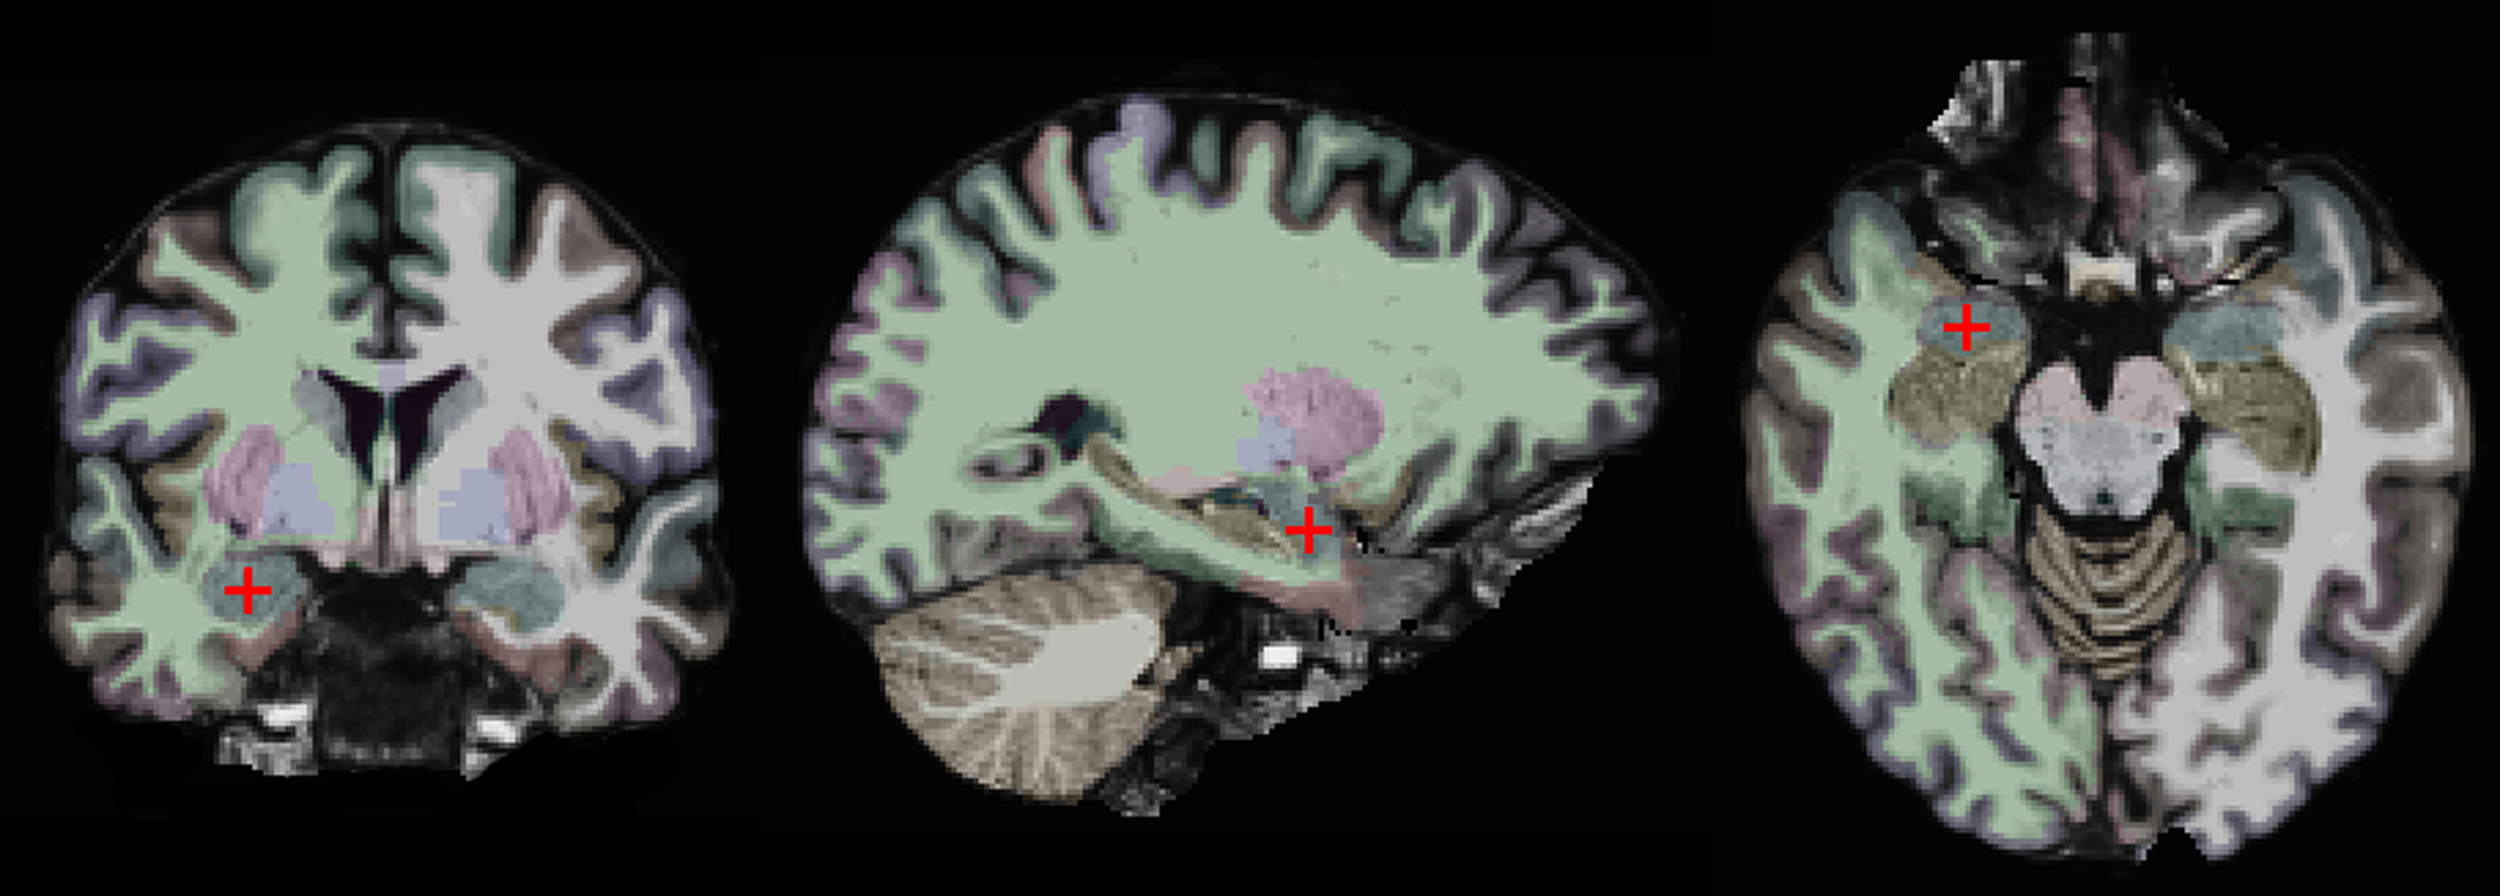

Our approach is based on a region-of-interest (ROI) analysis (Nieto-Castanon et al., 2003; Poldrack, 2007). Two anatomically defined ROIs, the left and right amygdalae, were automatically segmented in each subject's individual anatomical brain scan with the FreeSurfer (v. 5.1) image analysis suite, which is documented and freely available for download online (http://surfer.nmr.mgh.harvard.edu/) (Fischl et al., 2002, 2004). This segmentation is shown on one of our subjects in Figure 1. One advantage of using anatomically defined ROIs is that it eliminates the potential problem of circular analysis that exists for functionally defined ROIs (Poldrack, 2007; Kriegeskorte et al., 2009; Poldrack and Mumford, 2009; Vul et al., 2009). There are other advantages of using an ROI-based approach. First, it removes some variability due to noise by averaging over all voxels in the ROI. Second, it is more statistically powerful than other methods, since it controls for Type I errors by limiting the number of statistical tests. Third, it enables precise spatial correspondence of the region-of-interest across subjects, since it does not involve normalizing different brains to a common atlas (Poldrack, 2007).

Figure 1

Coronal, sagittal, and horizontal views of the brain of one study participant. The right amygdala is marked by a red crosshair and colored in blue. The other colors indicate different brain regions as automatically segmented by the FreeSurfer software.